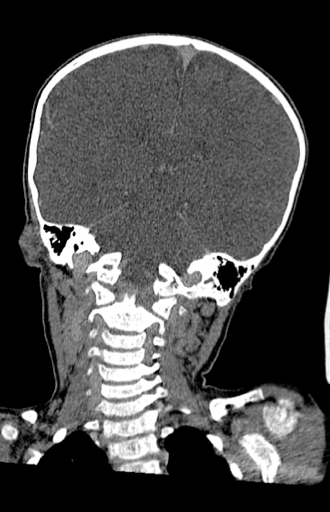

l’hydrocéphalie

il s’agit d’un mode de révélation non exceptionnel, parfois liée à

- une tumeur volumineuse

- ou avec dissémination méningée

- parfois associée à une pseudo-tumeur de petite taille, de nature vasculaire ou inflammatoire.